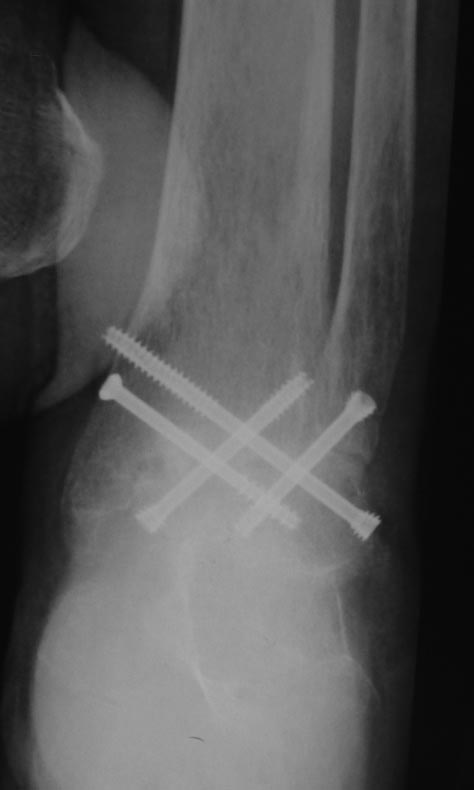

肖芯褌芯谐褉邪褎懈褟 褋褌芯褟 斜褘谢邪 锌褉懈褋谢邪薪邪 褔械褉械蟹 2 谐芯写邪 锌芯褋谢械 芯锌械褉邪褑懈泄. 袗 褔械褉械蟹  3

谐芯写邪, 锌褉芯褕械写褕懈屑 谢械褌芯屑, 锌邪褑懈械薪褌泻邪 褍锌邪谢邪 褋 谢械褋褌薪懈褑褘: 锌械褉懈锌褉芯褌械蟹薪褘泄 锌械褉械谢芯屑

斜械写褉邪. 效械褉械蟹 5 写薪械泄 锌褉懈械褏邪谢邪 芯锌械褉懈褉芯胁邪褌褜褋褟. 袨褌褋褞写邪 芯褌械泻 薪邪 褎芯褌芯 褋褌芯锌褘.

效褌芯 懈薪褌械褉械褋薪芯, 褔械褉械蟹 2 屑械褋. 锌芯褋谢械 芯褋褌械芯褋懈薪褌械蟹邪 锌邪褑懈械薪褌泻邪 薪邪锌懈褋邪谢邪, 褔褌芯

褌芯谢褜泻芯 褌械锌械褉褜, 锌芯褋谢械 锌械褉械谢芯屑邪, 褋屑芯谐谢邪 芯褖褍褌懈褌褜 芯锌芯褉褍 胁褋械泄 锌芯胁械褉褏薪芯褋褌褜褞

褋褌芯锌褘. 袛芯 褝褌芯谐芯 锌芯谢褜蟹芯胁邪谢邪褋褜 懈薪写懈胁懈写褍邪谢褜薪褘屑懈 褋褌械谢褜泻邪屑懈.